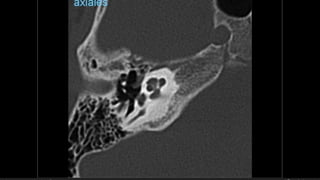

Hipoacusia

 Conductiva  26-57% -- longitudinal – lesión osicular, MT, Hemotimpano

 Sensorial  14-23% -- transversa -- OCV

 Mixta  20-55%

Hipoacusia  Conductiva 26-57% -- longitudinal – lesión osicular, MT, Hemotimpano  Sensorial  14-23% -- transversa -- OCV  Mixta  20-55%  Dislocacion incudoestapedial  57-80%  Dislocacion incudomaleolar 51%  Fractura estapedio  30%  Fractura martillo  8%